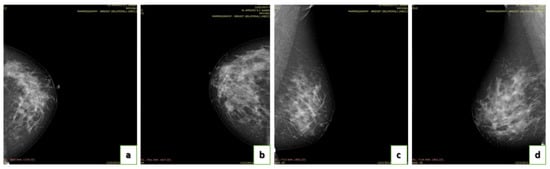

4.4. Breast Density

- A (0–25%): Almost entirely fatty indicates that the breasts are almost entirely composed of fat. One out of ten women has this result.

- B (25–50%): Scattered areas of fibroglandular density indicate some scattered areas of density, but most of the breast tissue is non-dense. Four out of ten women have this result.

- C (50–75%): Heterogeneously dense indicates that there are some areas of non-dense tissue but that most of the breast tissue is dense. Four out of ten women have this result.

- D (75–100%): Extremely dense indicates that nearly all breast tissue is dense. One out of each women has this result.